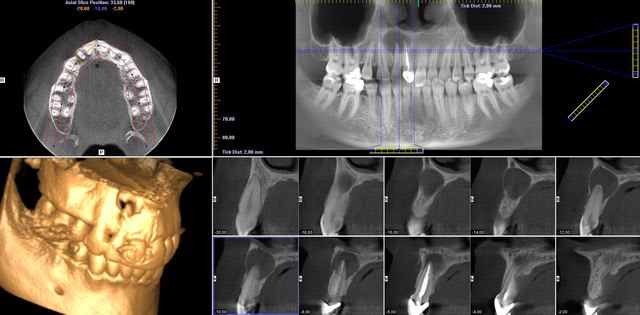

Je suis omnipraticien, je fais pas mal de 8 et 3 incluses, de kystes, de ROG, sinus et pose une petite centaine d’implants par an. Je me suis « offert » une Pano 3D en juillet après longue et mûre réflexion. En voici la teneur globale :

Je me suis évité de très mauvaises surprises en chir : en vrac, kyste apical 22,23,24 avec perfo nasale, perfo linguale sur un comblement alvéolaire de 36, des fractures radiculaires sagittales en pagaille, canal supplémentaire sur 33 ou34, fenestration de tables externes, etc…

SIRONA Orthophos avec Galliléos pour l'implanto, 2 licences (poste pano et secrétariat grand écran), le micro qui va avec et tout, 85 K€